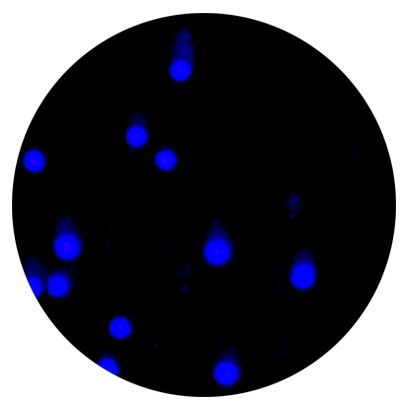

细胞活死染色